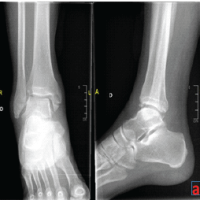

Post-operatively, from day 1, the patient was started on chest physiotherapy, incentive spirometry, and ankle pumping exercises. The patient was started on chemical deep vein thrombosis prophylaxis from post-operative day 2. The patient was started on in-bed mobilization and knee range of motion exercises for the first 2 weeks, and then started on non-weight-bearing mobilization of the right lower limb till the 6th week. After a 6-week post-operative period, the patient was started on full weight-bearing mobilization on the right side following postoperative 6-week X-ray evaluation (Fig. 4). There were signs of radiological union, and hence full weight-bearing mobilization on the right side was started after 6 weeks post-operative. There was no evidence of neurological deficit.